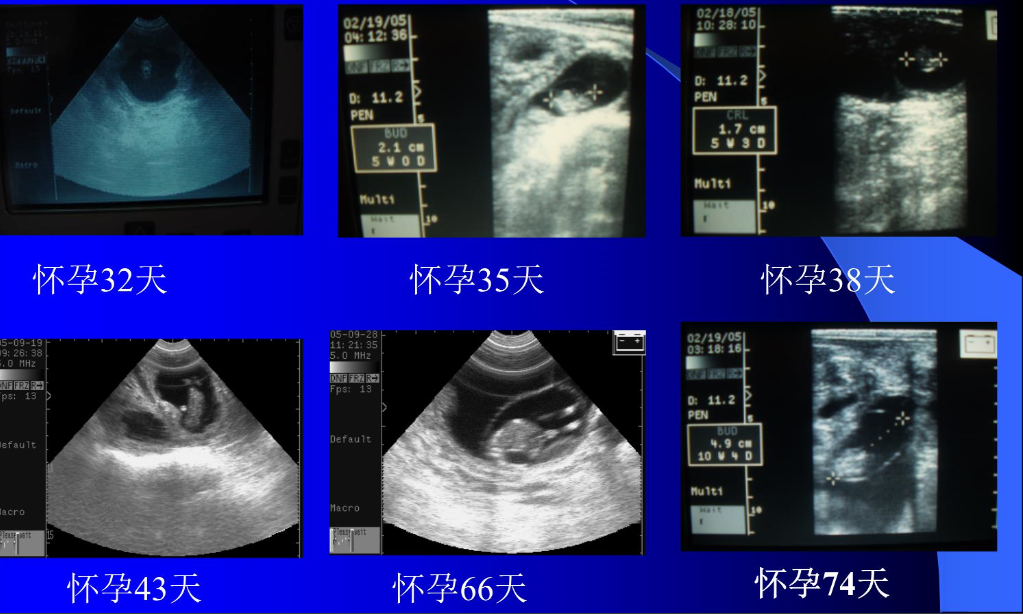

1、在操作过程中为避免操作失误,要先将直肠中的牛粪清除干净,牛粪会阻碍探头与直肠壁的耦合,影响操作效果;如果直肠中存在太多牛粪会造成牛努责,增加操作难度并加大应激。

2、在探头进入直肠前可先触碰一下子宫以了解其基本位置,节约操作时间,操作工程中要缓慢进行,避免因探头振动而造成牛努责。

3、另外还要区分胎囊、卵泡和膀胱,由于三者位置相近,并都呈无回声暗区,易造成判断失误;

4、探查部位应选择靠近生殖器官的部位,避免因胎囊沉于子宫角底部而造成失误。